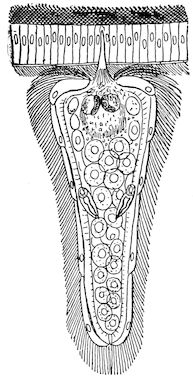

Fig. 8.—Transverse section through the middle region of the face in a pig suffering from osseous cachexia.

The fractures which occur so frequently during the osteoclastic phase have well-marked peculiarities. The extravasation of blood is trifling, and no callus forms, even when the ends of the bones are immobilised by external aid; if the ends are left free, they soon become worn and polished by rubbing against one another.

In the neighbourhood of the articulations and ligamentous insertions the periosteum soon undergoes change, and it is not uncommon to find sub-periosteal and intra-osseous extravasations of blood.

Germain has also noted in horses the disappearance of the intervertebral and articular cartilages, and the frequent occurrence of anchylosis, true or false.

18In the final stages, the bones may be cut with a knife, and a time arrives when bony tissue seems completely to have disappeared; thus, as shown in Fig. 8 herewith, it was possible to cut the entire head of a pig into thin slices without the slightest difficulty. All parts of the head had been affected by the softening change.

From the chemical point of view, the diminution in mineral salts and in phosphate of calcium has long been recognised, but the degree of this change varies according to the phase. In human beings the proportions have been estimated as follows: Normal bone, 50 to 80 per cent. of phosphate of calcium; bone in persons suffering from osteomalacia, 5 to 20 per cent. of phosphate of calcium. The changes in the ossein have not been carefully studied. We only know that histologically the ossein becomes fibrillar, and that chemically it no longer retains its normal composition.